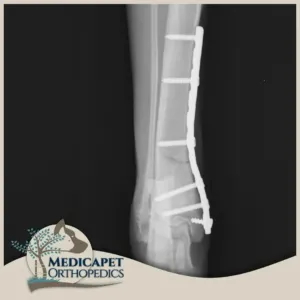

Plak Uygulamaları

Medicapet’de açık operasyon ve internal fiksasyon gerektiren kırıklarda yüksek kaliteli titanyum plaklar ve vidalar kullanıyoruz. Plak uygulamalarımızda kırık oluşan bölge eski konumuna getirildikten sonra kemiğe uygun plak tipi seçilerek bölgeye yerleştiriliyor, mümkin olan en az vidanın kullanılması ile kırığı onarıyor, gereken durumlarda iyileşmeden sonra implantı geri çıkarıyoruz. Plak uygulamalarımızdaki temel prensibimiz minimal invaziv yöntemleri kullanmaktır. Böylece mümkün olan en küçük boyuttaki kesiyi yaptığımız için iyileşme sürecini de hızlandırmış oluyoruz.